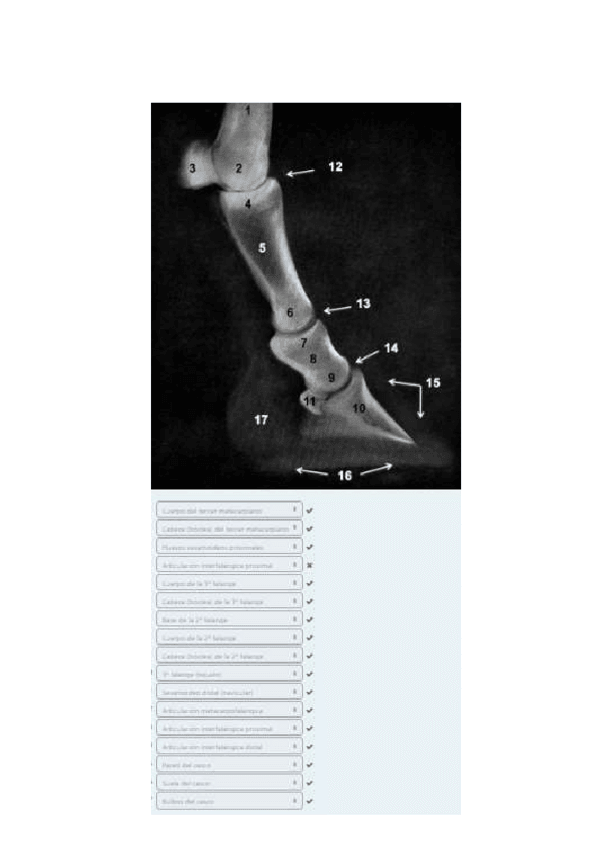

He publicado nuevos apuntes de 1º EMBRIOLOGÍA Y ANATOMÍA I: Radiografías práctica 6.pdf

8 páginas

He publicado nuevos apuntes de 1º EMBRIOLOGÍA Y ANATOMÍA I: Radiografías práctica 3.pdf

5 páginas

He publicado nuevos apuntes de 1º EMBRIOLOGÍA Y ANATOMÍA I: Radiografías práctica 5.pdf

10 páginas

He publicado nuevos apuntes de 1º EMBRIOLOGÍA Y ANATOMÍA I: Radiografías práctica 7.pdf

13 páginas

He publicado nuevos apuntes de 1º EMBRIOLOGÍA Y ANATOMÍA I: Radiografías práctica 8.pdf

12 páginas

He publicado nuevos apuntes de 1º EMBRIOLOGÍA Y ANATOMÍA I: Radiografías práctica 4.pdf

9 páginas